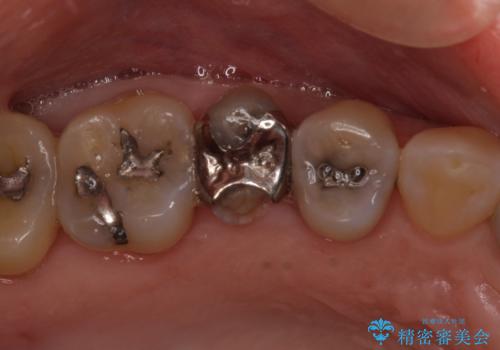

- 前歯のすきっぱを主訴にご来院された患者様です。他院でつめものやラミネートべニア(前歯の表面のみセラミックを貼り付ける)を行っていましたが、頻繁に外れることに悩まれており、クラウン(歯全体をセラミックがつつむ)をご希望されました。また、奥歯に大きな虫歯があり、歯が割れていたため、奥歯の治療も併せて行いました。

右上の歯に関しても、大きな虫歯があったため、前歯の経過観察の間に治療を行いました。